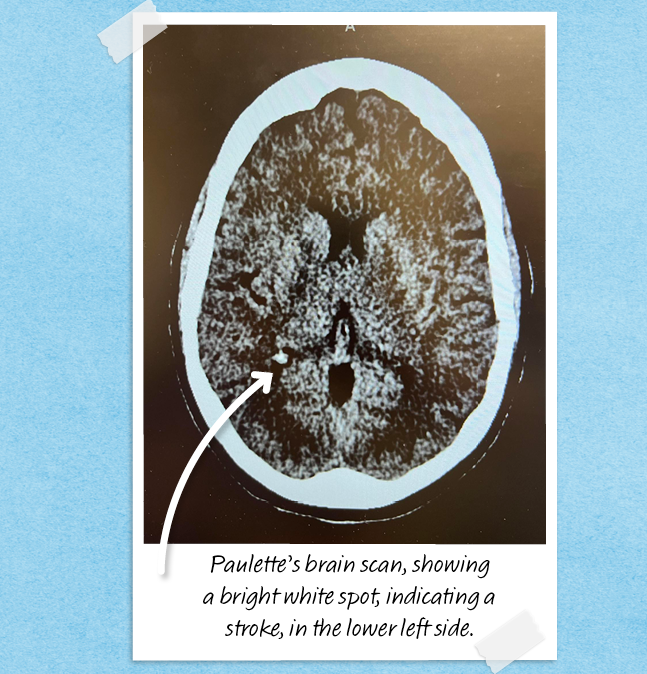

“In the ER, I was asked 1,000 questions — about stress and any recent weight changes — and hooked up to an IV. My symptoms weren’t consistent with a type of migraine called an ocular migraine that affects vision, so the staff performed a CAT scan. It didn’t find anything. Next, they did a CAT scan with contrast dye and that’s when they found the unmistakable white spot on my brain indicating one thing: a stroke.